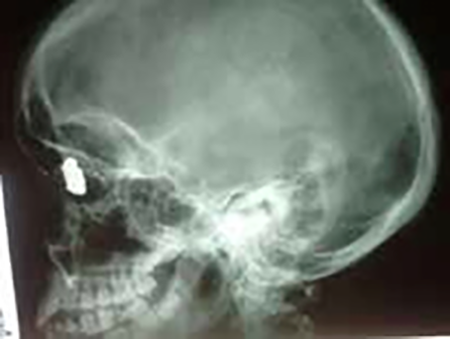

A.B.A., de 15 años de edad y sexo femenino. En la madrugada del 25/12/18 se encontraba caminando por la acera cuando de pronto se produce un intercambio de disparos entre dos masculinos que se desplazaban en motocicleta y otro a la vera del camino. Al escuchar las detonaciones, gira su rostro para ver la escena que ocurría unos 25 mts. del lugar donde se encontraba, cuando siente un impacto en cara anterolateral izquierda de su nariz e inmediatamente después percibe ausencia de visión en su ojo derecho. Concurre a institución especializada donde se practica tomografía computada y se opta por tratamiento conservador antibiótico y antiinflamatorio (amoxicilina-clavulánico y ketorolaco). Por proyectil extraído del TCS de otra persona afectada (trayecto en sedal) se presume calibre 22.

El 11 de enero de 2019 concurre a mi consulta con las imágenes y realizo el siguiente examen.

Inspección: Llama la atención la asimetría facial debido a encontrarse en OD con proptosis, borramiento parcial del surco órbito-palpebral, y en hipotropia e hipoglobo con motilidad anulada en la mirada hacia los campos superiores y limitaciones en los movimientos inferiores de abducción y aducción. La pupila se encontraba en una midriasis arreactiva.

Equimosis palpebral inferior. Ptosis con menor tamaño de la hendidura interpalpebral. Córnea sin sensibilidad. El OI presentaba movimientos plenos e irrestrictos y con una pupila reactiva y su apariencia era totalmente normal. Se observaba cicatriz redondeada en la cara anterolateral izquierda y superior de la pirámide nasal, la cual se presume como el orificio de entrada del proyectil y sin orificio de salida. Ligera proptosis (Figura 1).

Se solicitaron Rx de cráneo frente perfil, MNP y FNP y tomografía computada, constatándose la presencia de proyectil en ángulo supero-interno de órbita y esquirlas diseminadas. En su pasaje desde su ingreso en la cara anterolateral izquierda y superior de la pirámide nasal el proyectil se fue fragmentando dejando partículas plúmbicas diseminadas. No habiendo signos infecciosos se discontinúa el antibiótico y se mantiene el antiinflamatorio (Figuras 2 y 3).